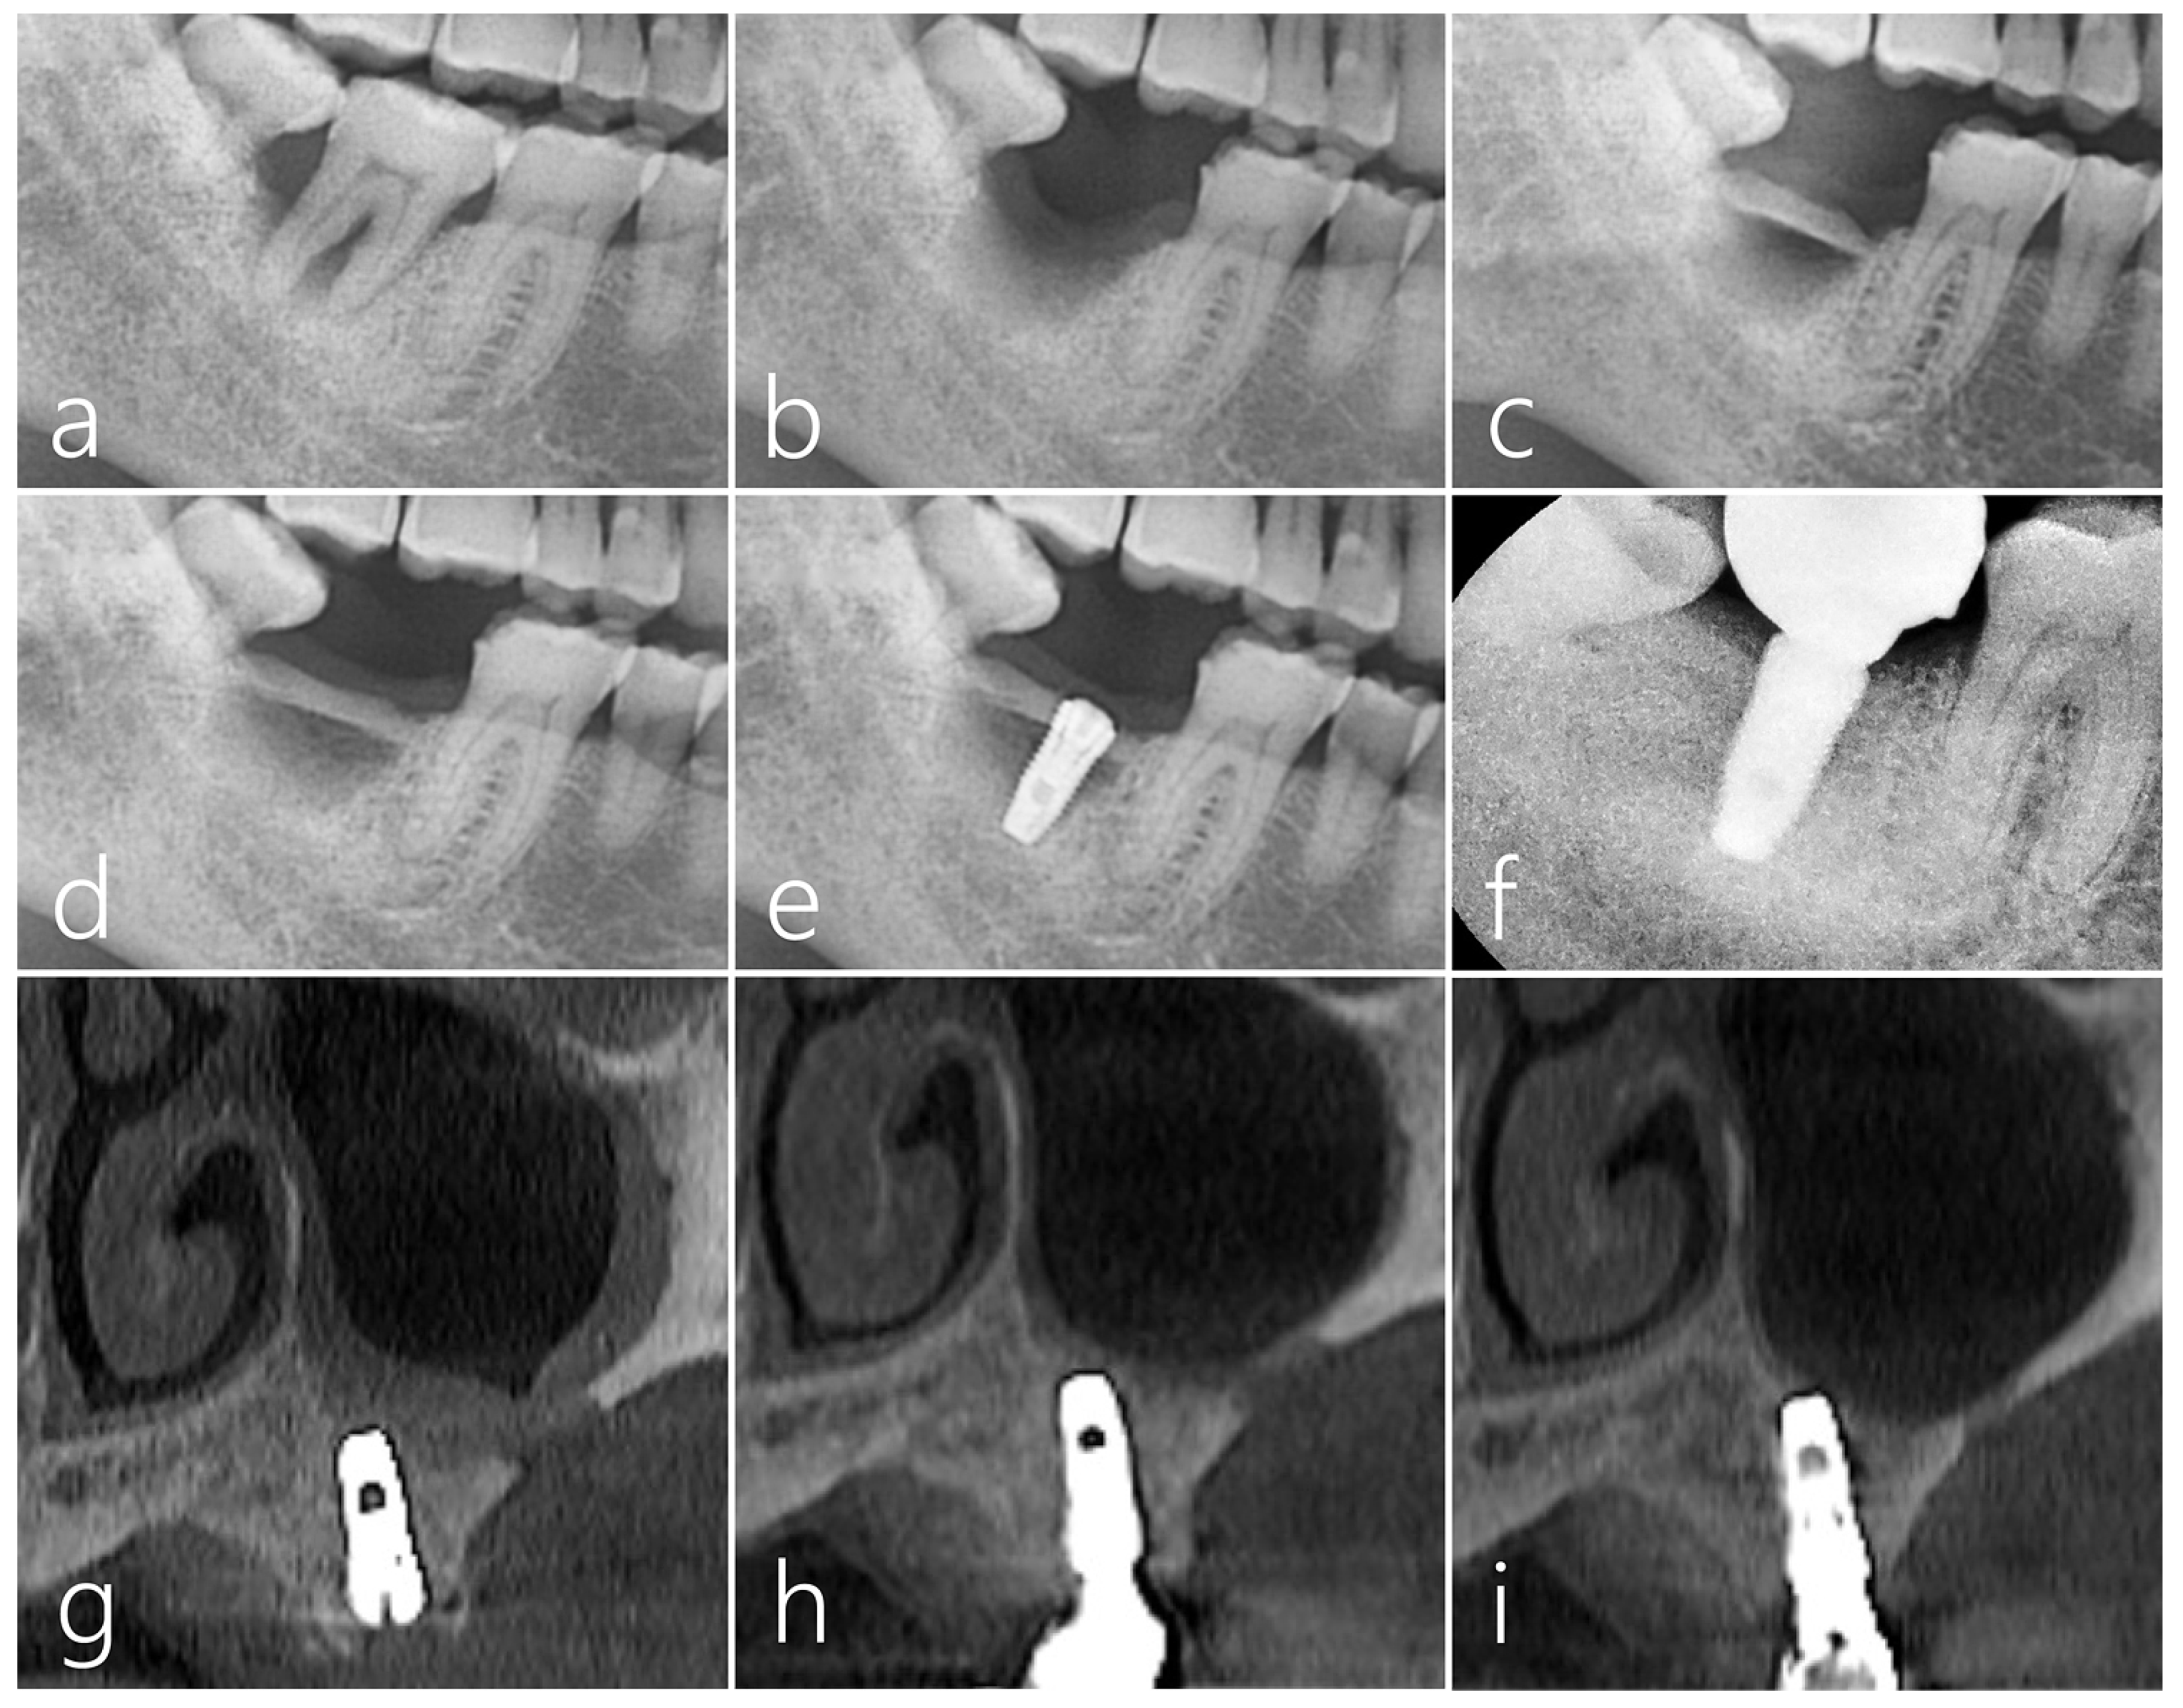

2.4. Case 4

A healthy 42-year-old male non-smoker patient presented himself to the clinic for re-implantation of a #16 implant. The implant #16, which was placed 10 years ago, developed peri-implantitis with severe bone resorption and suppuration (Figure 9a). The failing implant was removed, and another implant was placed concurrently with additional transcrestal sinus floor elevation. No perforation of the sinus membrane occurred during the sinus floor elevation (Figure 9b). The removed bone from the window was used as a bone bridge for the vertical ridge augmentation of the explantation site (Figure 9c). The space between the bone bridge and the explantation defect was filled with particulate bone (Osteon III, Genoss, Suwon, Republic of Korea). The bone bridge was fixed to the adjacent native bone using the press-fit method (Figure 9d) and covered with a resorbable collagen membrane (Figure 9e). The mucoperiosteal flap was closed.

Figure 9.

Case 4 (a) The patient #16 implant had peri-implantitis with severe bone resorption; (b) For a future successful implant replacement, the failed implant was removed and a transcrestal sinus floor elevation using Summers osteotome was performed simultaneously. (c) Sinus mucosa did not perforate during sinus floor elevation; (d) The removed lateral sinus access window was used as a bone bridge for vertical ridge augmentation of the explantation site. The dead space between the bone bridge and the explantation defect was filled with particulate bone. A bone graft was also performed in the elevated sinus. Bone bridges were fixed to the adjacent crestal bone by the press-fit method; (e) The graft site was covered with a resorbable collagen membrane. The flap was closed; (f) During the healing period, there was no special event at the bone graft site of the maxillary sinus, but the wound was partially opened, and healing was somewhat delayed; (g) After 5 months, an osteotomy was performed for implant site preparation. After thoroughly removing the infiltrated soft tissue, a Ø 4.3 × 10 mm SLA-textures implant was placed. At the time of the implant placement, the existing bone bridge was well integrated with the surrounding native bone and did not move. The implant was positioned 1.0 mm subcrestally to the platform. The flap was closed with 4-0 nylon. Uncovering was performed after 4 months, and the healing process was uneventful; (h) After 2 months, the final prosthesis was placed, and after 1 year, the crestal bone level was not resorbed, and chewing function was restored.

During the healing period, there were no adverse events at the bone graft site, but the wound was partially opened, and healing was delayed (Figure 9f). After 5 months, the mucoperiosteal flaps were reflected for implant placement. The bone bridge seemed to have resorbed slightly and soft tissue ingrowth was observed. However, the existing bone bridge was well integrated with the surrounding native bone and did not show any mobility. An osteotomy was prepared for a Ø 4.3 × 10 mm SLA-textures implant (Implantium, Dentium, Suwon, Republic of Korea), and the fixture was placed with good initial stability. The implant was positioned 1.0 mm subcrestally to the platform, and the healing abutment was inserted. (Figure 9g). The flap was closed with 4-0 nylon. Uncovering was performed after 4 months, and the healing process was uneventful. After 2 months, the final prosthesis was delivered. One year after the prosthesis was delivered, no resorption was observed in the crestal bone level, and chewing function was restored (Figure 9h) (Table 1).